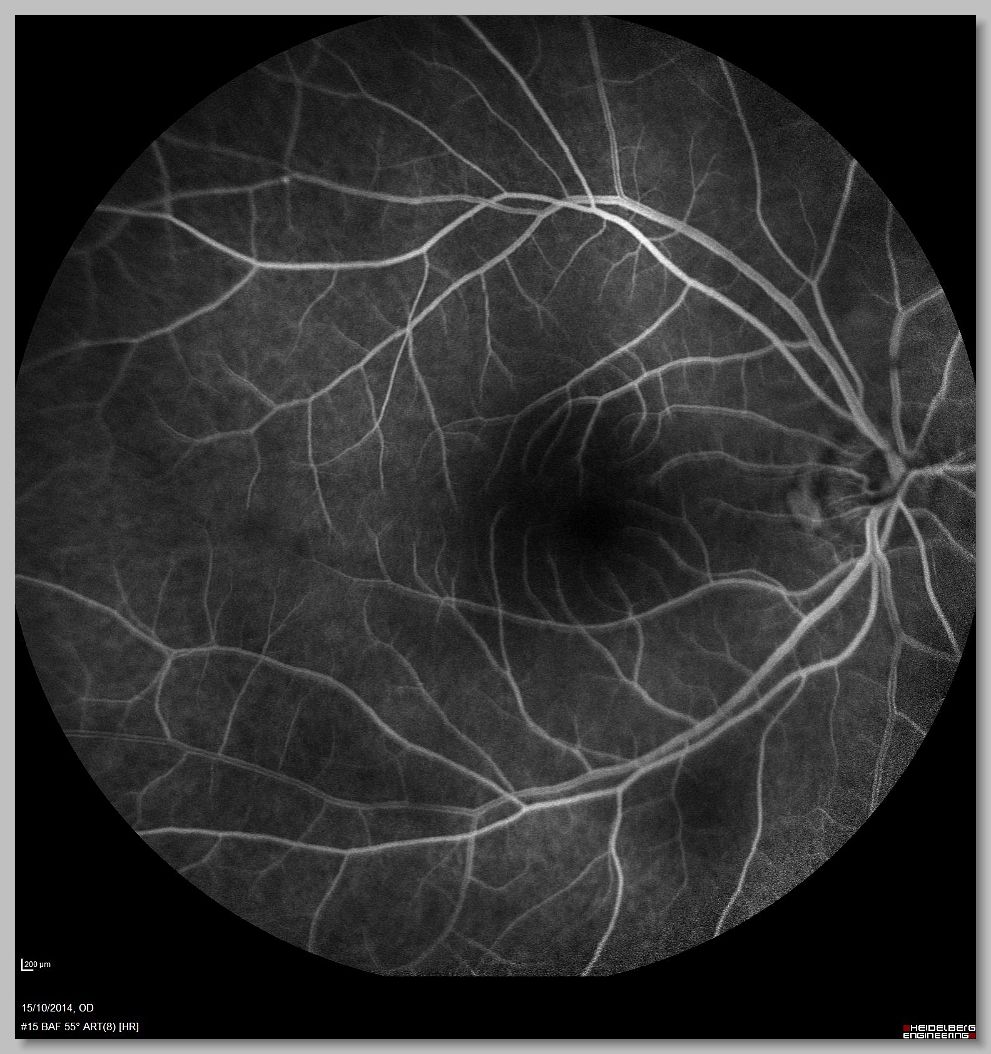

FA 001 FA 002 FA 003 FA 004

FA 005 FA 006 FA 007 FA 008

FA 009 FA 010 FA 011 FA 012

FA 013 FA 014 FA 015 FA 016

FA 017 FA 018 FA 019 FA 020

FA 021